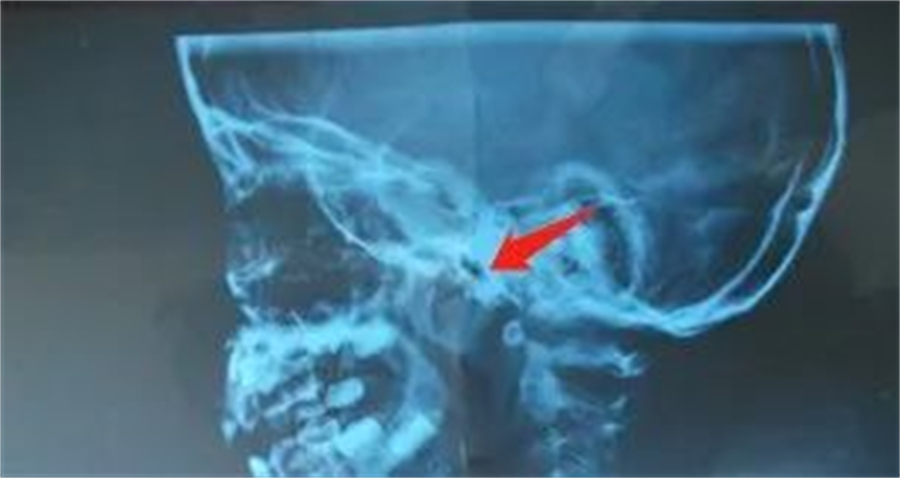

鼻咽侧位片的腺样体肥大